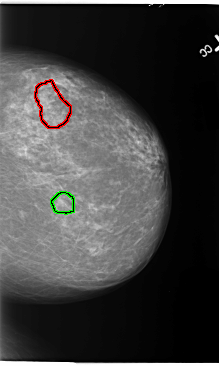

B_3110_1.LEFT_CC

FILE: B_3110_1.LEFT_CC.OVERLAY

TOTAL_ABNORMALITIES 2

ABNORMALITY 1

LESION_TYPE CALCIFICATION TYPE PUNCTATE-PLEOMORPHIC DISTRIBUTION CLUSTERED

ASSESSMENT 4

SUBTLETY 3

PATHOLOGY BENIGN

TOTAL_OUTLINES 1

BOUNDARY

ABNORMALITY 2